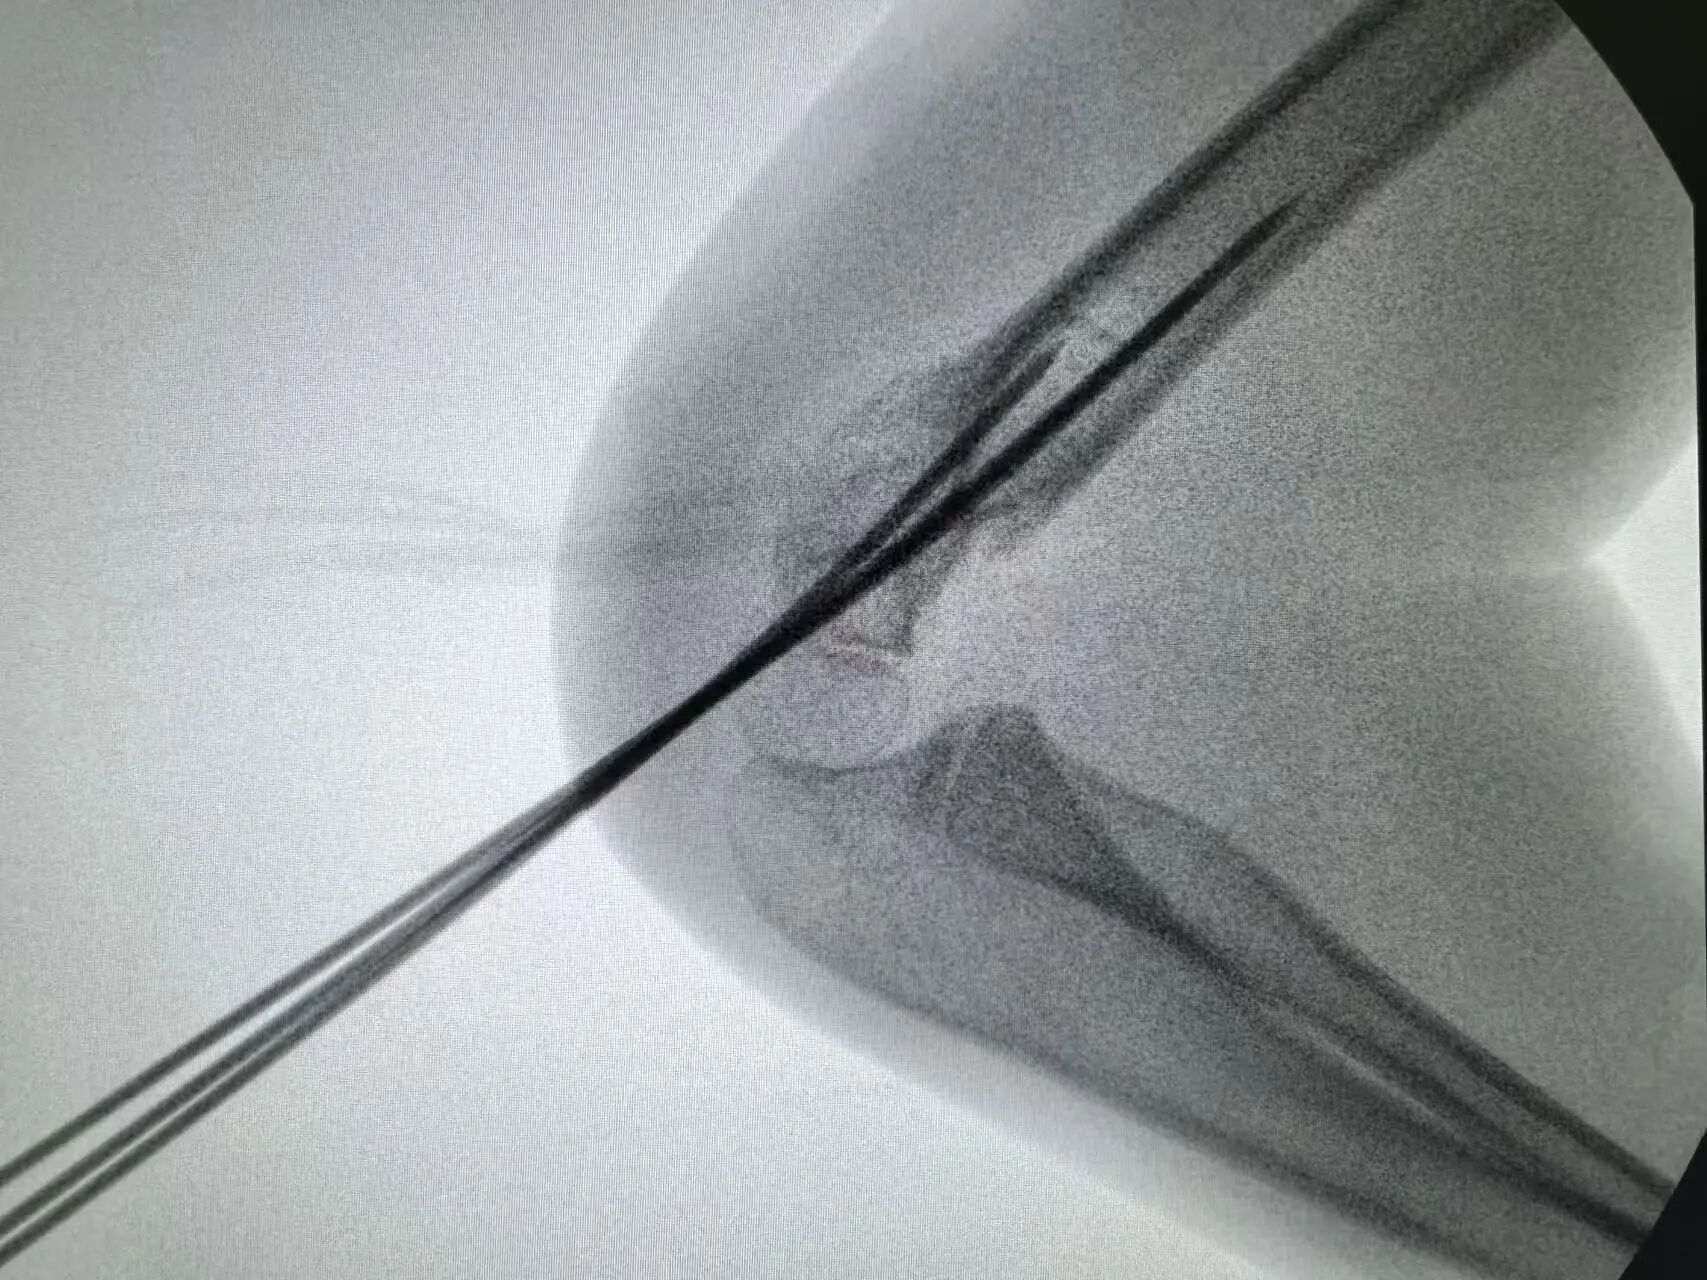

同样“抢时间”的还有小罗和小周的治疗:4岁小罗9月15日深夜入院,10小时后顺利手术;7岁小周同一晚受伤,也在10小时内完成肱骨髁上骨折闭合复位经皮固定术。6岁小郑更是创下“4小时极速手术”纪录——早晨7点40分受伤,8点多入院,11点多手术结束,当天下午就能躺上网课。

“我们的目标是‘24小时内完成急诊手术’,尽量让孩子少耽误一节课。”骨伤科手外·儿骨·烧伤整形组主任陈孝均教授介绍,为了实现这个目标,团队制定了专属流程:孩子入院后,急诊优先开具检查单,放射影像科快速出片;骨科医生同步评估病情,确定手术方案;麻醉科提前做好准备,只要术前检查合格,立刻安排手术——哪怕是深夜或周末,团队也随时待命。

这种“加速度”不仅为学习抢时间,更符合儿童骨折治疗的“黄金原则”:“儿童骨骼生长快,早期复位固定能减少畸形风险,恢复也更快。”陈孝均补充道。